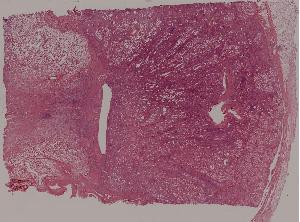

77. Chronic pyelonephritis